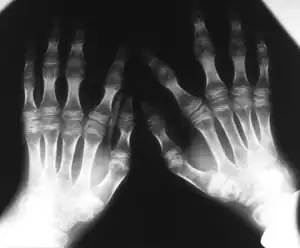

Kniest dysplasia- Hands demonstrate flattening of metacarpal epiphyses, carpus has a disorganized aspect

• X-rays - X-ray images will allow the physician to have a closer look on whether or not the bones are growing abnormally.

The images taken will help to identify any bone anomalies. Two key features to look for in a patient with Kniest dysplasia is the presence of dumb-bell shaped femur bones and coronal clefts in the vertebrae. Other features to look for include: